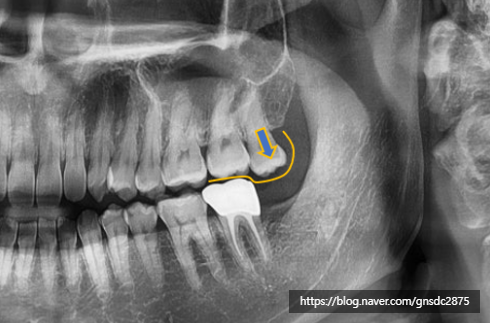

다음 환자분은 위 사랑니는 뽑지 않고

아래 사랑니만 발치한 상태로,

위쪽 잇몸에서 통증을 느끼시고

강남레옹치과에 방문해주셨습니다.

사진을 봐도 위 사랑니가 많이 내려온 상태입니다.

위 사랑니가 맞물리는 아래 치아가 없자

점점 내려와 잇몸에 자극을 주고 있었습니다.